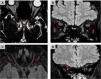

The aim of this work is to provide a diagnostic approach to the potential causes of optic neuropathy, focusing on the radiological findings associated with this pathology. Various etiologies have been identified, including inflammatory and demyelinating optic neuritis, developmental and hereditary diseases, neurodegenerative disorders, infectious conditions, post-traumatic causes, ischemic optic neuropathy (with anterior ischemic optic neuropathy being the most common form), and neoplastic etiologies. Optical coherence tomography and magnetic resonance imaging play a fundamental role in the diagnosis of optic neuropathy, allowing to distinguish patterns of optic nerve involvement. These studies are essential to locate and characterize the different pathologies, increasing the precision of the diagnosis in diseases presenting optic neuropathy as the main symptom. In conclusion, the findings obtained from magnetic resonance imaging are essential in the differential diagnosis of optic nerve diseases, aiding in the localization and characterization of various pathologies affecting either the optic pathway alone or multiple levels of the central nervous system and thereby increasing diagnostic accuracy.